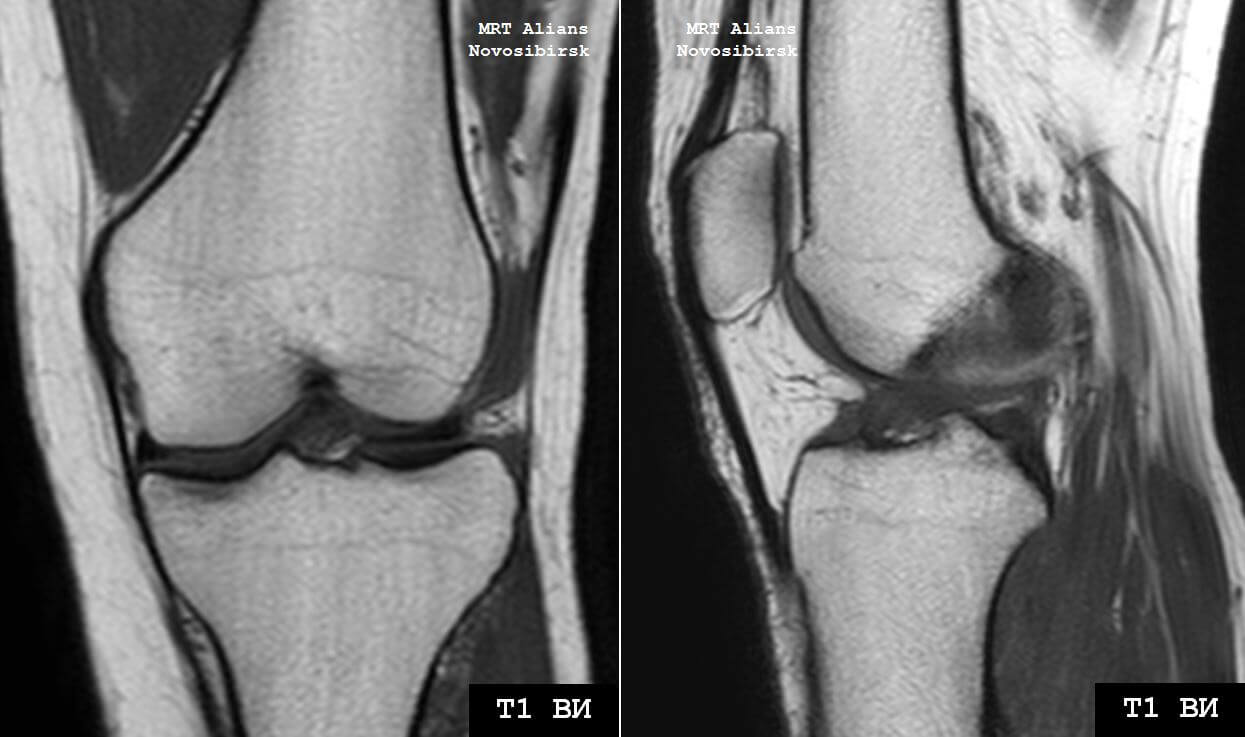

Медицинские снимки: рентген коленного сустава при остеопорозе